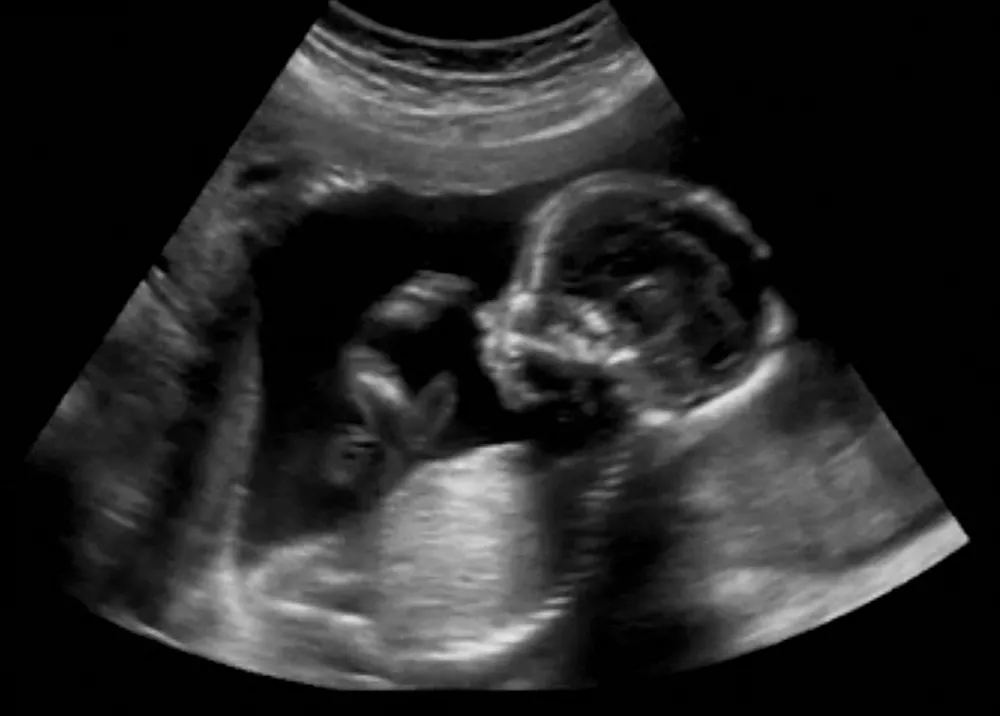

Normalnie, miała badania prenatalne. Na tzw. USG „połówkowym” lekarzowi coś nie nie podobało - nerki, płuca, brzuch czy serce…

Brzuch się rozcina i wyciąga dziecko?

Nie, to by było działanie zbyt inwazyjne. Kierujemy się zasadą, że lecząc dziecko staramy się minimalizować ryzyko dla matki. Zabieg wygląda tak, że przez brzuch kobiety wprowadza się do serca dziecka grubą igłę, a przez nią specjalny cewnik z balonem. Można nim poszerzyć zwężoną zastawkę. Albo wszczepić stent, czyli taką rurkę, przez którą będzie płynąć krew. Taki sam, jaki wszczepia się u dorosłych do naczyń wieńcowych.

Serce bije cały czas?

Jasne, około 140 uderzeń na minutę. Jest to bardzo trudny zabieg, bo nie dość, że się wszystko rusza, serce bije, matka oddycha, to jeszcze to serce jest bardzo malutkie. W 20 tygodniu ciąży jest wielkości pięciogroszówki. Ale nawet w takim małym sercu już można bardzo dużo zrobić.

Niekoniecznie, diagnostyka prenatalna to szerokie pojęcie. Najważniejsze jest badanie ultrasonograficzne dziecka.

Zasadniczo są to trzy badania USG w okresie ciąży. Pierwsze między 11 a 14 tygodniem ciąży, nazywane „genetycznym”. Potem tzw. „połówkowe”, około 20 tygodnia ciąży, i następnie około 30 tygodnia.